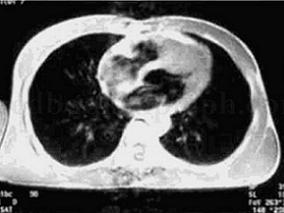

1小时条评论一、病情介绍 患者男性,46岁。 主诉:咳嗽、咳痰、活动后气短3个月。 现病史:患者于2007年12月感冒后出现咳嗽、咳白色黏痰,同时出现活动后气短,当时无胸闷痛、心悸等,未引起重视,2008年2月患者咳嗽、咳痰加重,不能平卧,伴咯血,量不多,同时出现水肿、...